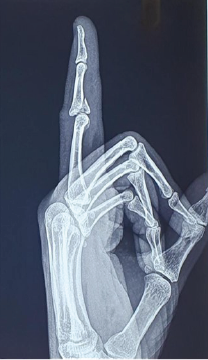

Dynamic External Fixation Using Suzuki Frame for Intra-articular Middle Phalanx Base Fracture with Dorsal Subluxation: A Case Report

Bibin Thankanadar Amaravathy , Sasi Kumar

………………………………p.170-173